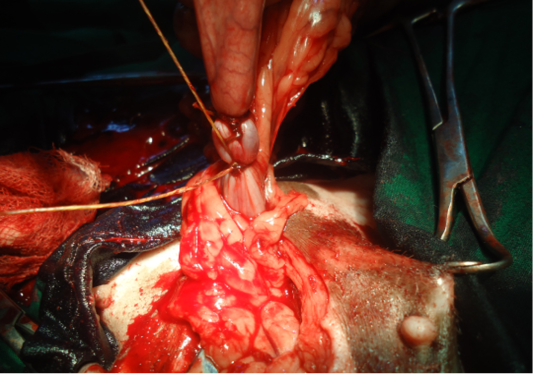

Figure 5

Ligating uteus